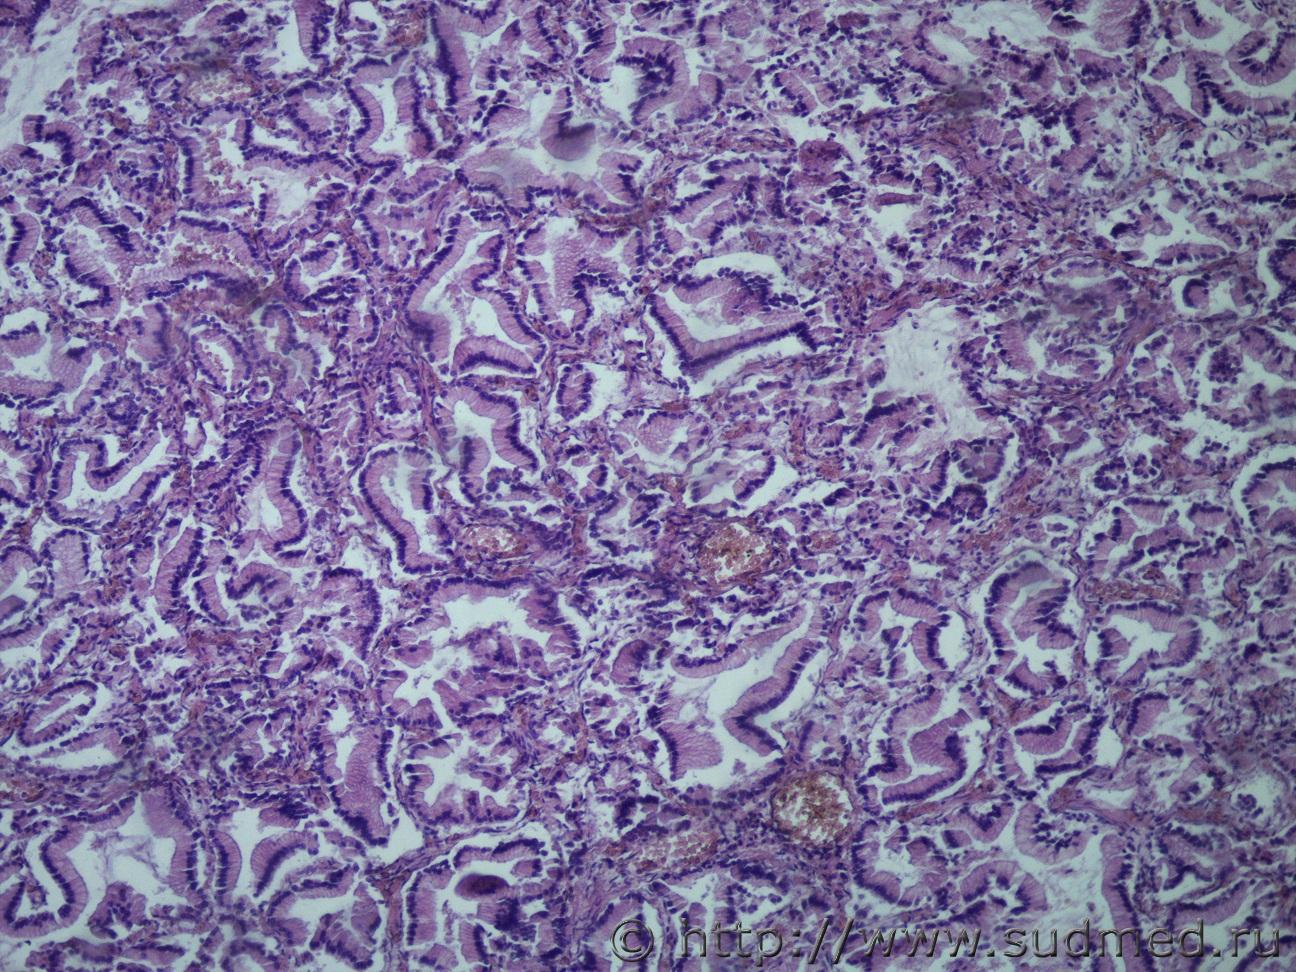

Ув. коллеги, сегодня в рубрике опухоль поджелудочной железы с метастазами в легкие. Муж, 80лет.

Легкие Судебная медицина - Прикрепленное изображениеСудебная медицина - Прикрепленное изображениеСудебная медицина - Прикрепленное изображение ПЖ Судебная медицина - Прикрепленное изображениеСудебная медицина - Прикрепленное изображениеСудебная медицина - Прикрепленное изображениеСудебная медицина - Прикрепленное изображение

Похоже на муцинозную цистаденокарциному? В легких очень красивый эпителий, а вот в поджелудочной такого эпителия очень мало(((

Похоже на муцинозную цистаденокарциному?

Да.

В гист.Акте печатайте без "цист". Просто, "муцинозная аденокарцинома".